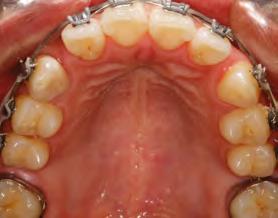

52 | SONRIENDO AL FUTURO

Tratamiento ortodóncico en paciente adulto tratado con extracciones de primeros molares permanentes. Reporte de caso

en paciente adulto tratado con extracciones de primeros molares permanentes. Reporte de caso